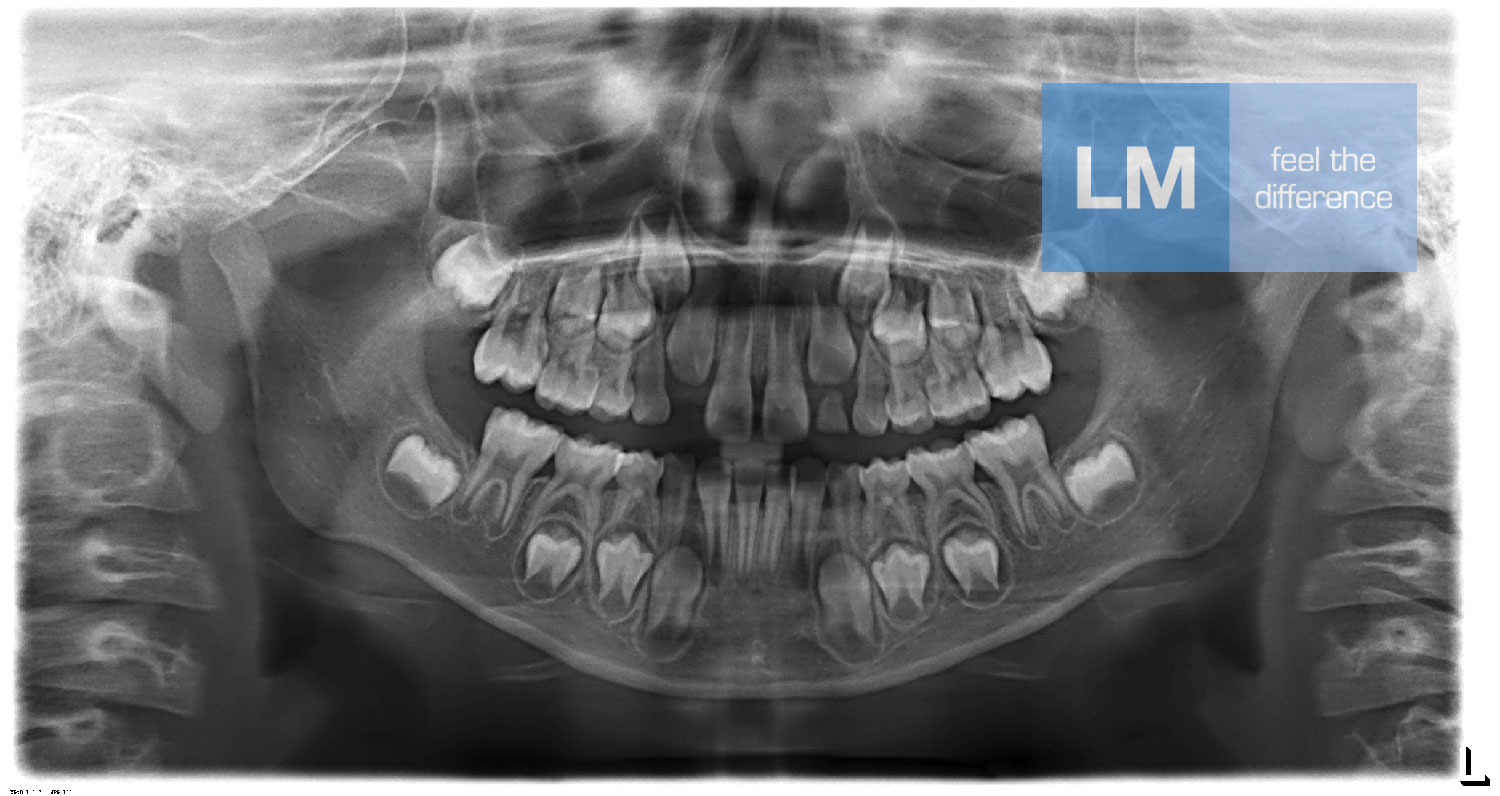

演示图片1

牙齿结构检测结果

自动检测牙齿结构

自动检测

AI自动识别曲面断层片中的关键解剖标志点